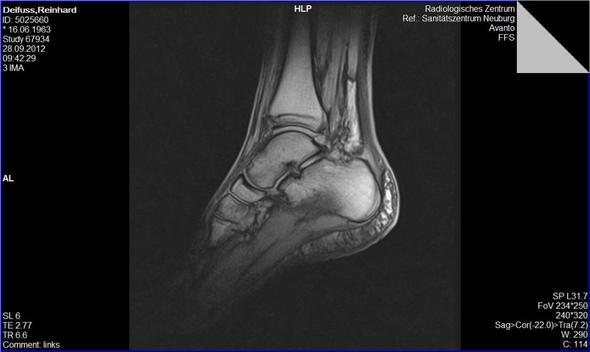

Chronik Einer Sprunggelenkfraktur Sky Junkies